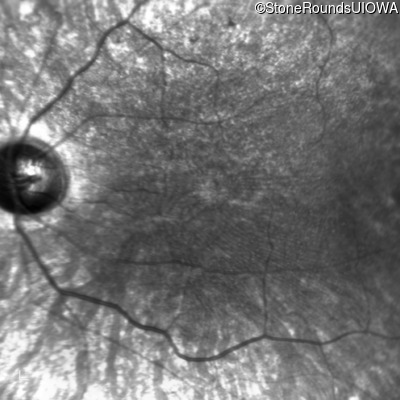

This 21 year old man first had difficulty seeing the blackboard in the 5th grade. Two years later he began having difficulty seeing in dim light. In high school he was approximately 50 pounds overweight, but was able to lose that weight with a strict diet.

| Bardet Biedl Syndrome | BBS1 | Met390Arg ATG>AGG | Arg277Lys AG(G)>AA(G) | AR |